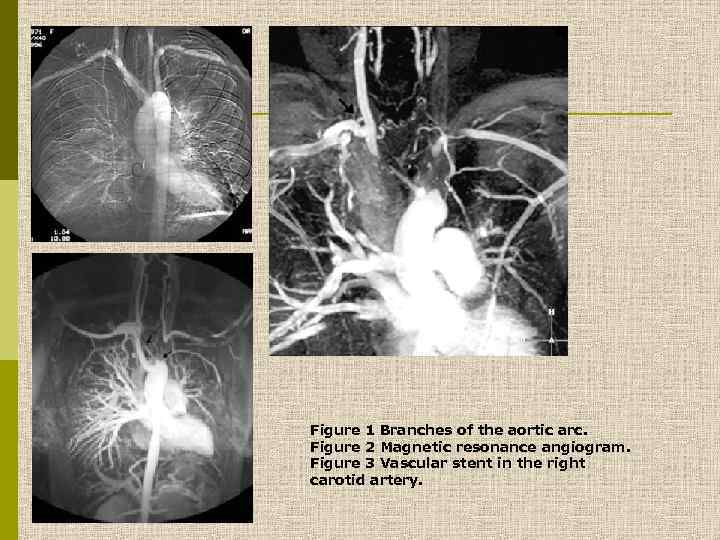

Окклюзия левой подключичной артерии вскоре после её отхождения от аорты. Результат – отсутствие пульса на левой руке. В процесс чаще вовлекается дуга аорты и отходящие от нее коронарные артерии, подключичные и почечные артерии. В артериях – гранулематозное воспаление, аневризмы и расслаивание стенки. В поздних стадиях – фиброз. Иногда поражаются легочные артерии.

Figure 1 Branches of the aortic arc. Figure 2 Magnetic resonance angiogram. Figure 3 Vascular stent in the right carotid artery.